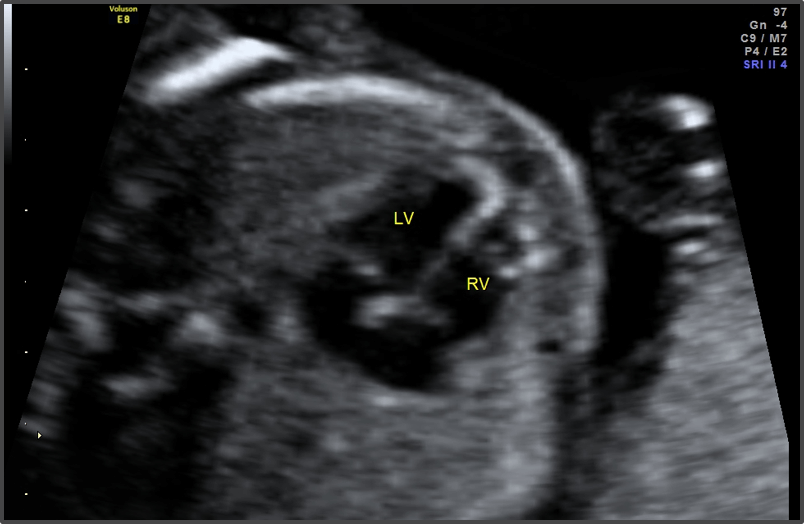

Baby Development

Baby can now hear sounds from the outside world.